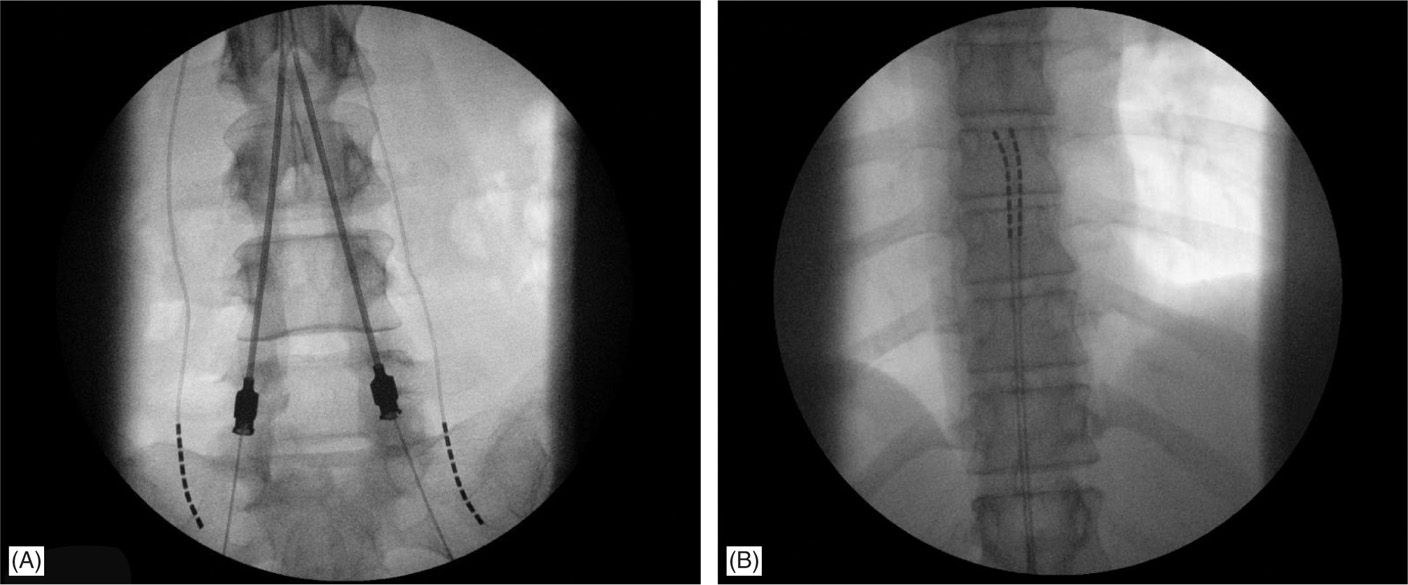

From www.researchgate.net

Two low thoracic spinal cord stimulator leads. Download Scientific Dual Lead Spinal Cord Stimulator Cpt Check national and local policies. Coding and payment guide for medicare reimbursement: The ama cpt has defined simple intraoperative or subsequent programming of neurostimulator. The lead implantation codes 63650 and 63655 may be used for both the trial and permanent implant stages. Saluda medical offers several resources for coding, coverage, and payment information for spinal cord stimulation. Cpt® 63650 can. Dual Lead Spinal Cord Stimulator Cpt.